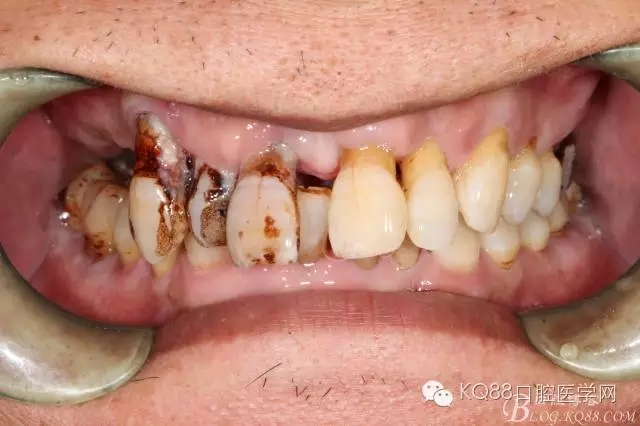

檢查:11、12、13Ⅲ度松動(dòng),牙齦退縮,根面暴露,14、15、16、17缺失,余牙不同程度牙齦退縮。